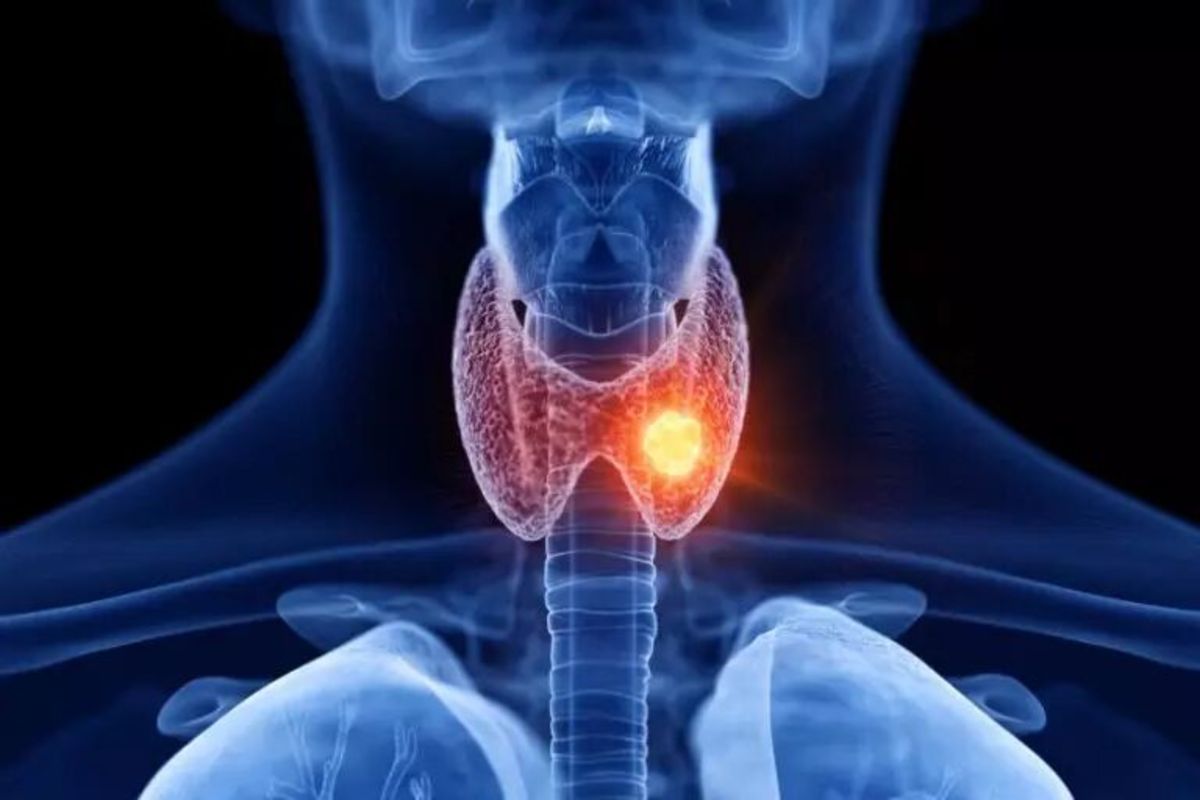

کم کاری و پرکاری تیروئید چه فرقی با هم دارند؟

به گزارش مجله خبری نگار،پرکاری تیروئید عارضهای است که در آن غده تیروئید، هورمونهایی بیشتر از حد نیاز بدن تولید و ترشح میکند. هورمونهای اصلی که تیروئید میسازد شامل ترییدوتیرونین (T۳) و تیروکسین (T۴) میشوند. پرکاری تیروئید میتواند بر تمام بدن اثر بگذارد و عارضهای است که باید توسط پزشک درمان شود. ضمناً پرکاری تیروئید در میان خانمها شایعتر است.

علائم پرکاری تیروئید

پرکاری تیروئید علائم بسیار زیادی میتواند داشته باشد، زیرا بر تمام قسمتهای بدن اثر میگذارد. البته همهٔ علامتها در همهٔ موارد این عارضه دیده نمیشود یا خیلی از این علائم همزمان ظاهر نمیشوند:. ضربان تند قلب. احساس رعشه و یا اضطراب. کاهش وزن. افزایش اشتها. اسهال و اجابت مزاج مکررتر. تغییرات بینایی. نازک شدن و گرمی و رطوبت پوست. تغییرات در قاعدگی. عدم تحمل نسبت به گرما یا تعریق زیاد. مشکلات خواب. تورم و بزرگشدن جلوی گردن در اثر بزرگشدن غده تیروئید (گواتر). ریزش مو و تغییرات در بافت مو. بیرونزدگی چشمها (در بیماری گریوز دیده میشود). ضعف عضلانی. بیقراری. مشکل در تمرکز. خارش. رشد سینه در مردان. سرگیجه. تنگی نفس

علتهای پرکاری تیروئید

عوارض و شرایطی که میتوانند سبب پرکاری تیروئید شوند شامل موارد زیر میشوند:. بیماری گریوز: در این اختلال، سیستم ایمنی بدن به غده تیروئید حملهور میشود و در نتیجه تیروئید، هورمون زیادی تولید میکند. بیماری گریوز یک عارضهٔ وراثتی میباشد، یعنی اگر عضوی از خانواده شما بیماری گریوز داشته باشد، این احتمال وجود دارد که شما و دیگر اعضای خانوادهتان نیز به این بیماری دچار شوید. بیماری گریوز، شایعترین علت پرکاری تیروئید بوده و ۸۵ درصد موارد را شامل میشود.. گرهها یا ندولهای تیروئید: یک ندول تیروئید، برآمدگی متشکل از سلولهایی در غده تیروئید است. این ندولها یا گرهها میتوانند هورمونهای بیشتری از حد نیاز بدن تولید کنند. ندولهای تیروئید بهندرت سرطانی میشوند.. تیروئیدیت: به التهاب غده تیروئید، تیروئیدیت گفته میشود که میتواند با درد یا بدون درد باشد. تیروئیدیت ممکن است در عرض یک سال بعد از زایمان به وجود بیاید (تیروئیدیت پس از زایمان). بعد از ابتلا به تیروئیدیت، غده تیروئید احتمالاً نمیتواند خودش را بازیابی کند و منجر به پرکاری تیروئید خواهد شد.. مصرف زیاد یُد: اگر در معرض پرکاری تیروئید باشید و یُد زیاد مصرف کنید (از طریق رژیم غذایی یا داروها)، باعث میشود غده تیروئیدتان هورمون تیروئید زیاد تولید کند. یُد یک ماده معدنی است که غده تیروئید از آن برای تولید هورمون تیروئید استفاده میکند. دریافت یُد بهصورت تزریقی هم میتواند باعث پرکاری تیروئید شود. آمیودارون (داروی تخصصی قلب) نیز دارویی است که حاوی مقدار زیادی یُد بوده و میتواند منجر به پرکار شدن تیروئید شود.. تومورهای تخمدان یا بیضه. تومورهای خوشخیم تیروئید یا غده هیپوفیز. دریافت مقدار زیاد تترایدوتیرونین از طریق رژیم غذایی یا دارو

پرکاری تیروئید چگونه تشخیص داده میشود؟

پزشک از چند طریق میتواند پرکاری تیروئید را تشخیص بدهد:. معاینهٔ فیزیکی گردن تا ببیند غده تیروئید بزرگتر از حد نرمال است یا نه. آزمایش خون برای بررسی سطح هورمون تیروئید در بدن. تستهای تصویری برای دیدن غده تیروئید

پرکاری تیروئید چگونه درمان میشود؟

دارودرمانی

داروهای آنتی تیروئید مانند متیمازول، تولید هورمون تیروئید را متوقف میکنند. دارودرمانی، شیوهٔ معمول درمان پرکاری تیروئید است.

یُد رادیواکتیو

ید رادیواکتیو برای درصد زیادی از افرادی که به پرکاری تیروئید دچارند تجویز میشود. در این شیوه، سلولهایی که هورمون تولید میکنند به طور موثر نابود میشوند. عوارض جانبی معمول یُد رادیواکتیو شامل خشکی دهان، خشکی چشمها، گلودرد و تغییرات در حس چشایی میشوند. بعد از درمان با یُد رادیواکتیو لازم است برای مدت زمان کوتاهی بیمار از سایر افراد جدا باشد تا پرتوها به دیگران منتشر نشوند.

عمل جراحی

ممکن است بخشی از غده تیروئید یا کل آن طی عمل جراحی برداشته شود. سپس لازم است بیمار مکملهای هورمون تیروئید مصرف نماید تا به کمکاری تیروئید دچار نشود. همچنین مهارکنندههای بتا مانند پروپرانول میتوانند به کنترل ضربان تند قلب، تعریق، اضطراب و فشارخون بالا کمک کنند. بیشتر افراد به این شیوه درمان پاسخ خوبی میدهند.

برای بهبود علائم پرکاری تیروئید چه میتوانید بکنید؟

به گزارش وب گاه تبیان، داشتن رژیم غذایی مناسب، با تمرکز بر کلسیم و سدیم بسیار مهم است، خصوصاً برای پیشگیری از پرکاری تیروئید. با مشورت پزشکتان یک دستورالعمل غذایی مناسب تهیه کنید، داروهای تجویز شده را مصرف کرده و ورزش کنید.

پرکاری تیروئید میتواند باعث ضعیف و نازک شدن استخوانها نیز بشود که در نهایت پوکیاستخوان را به دنبال خواهد داشت. مصرف ویتامین D و کلسیم، حین و بعد از درمان به تقویت استخوانها کمک میکند.

تفاوت پرکاری تیروئید با کمکاری تیروئید

پرکاری تیروئید و کمکاری تیروئید هر دو عوارضی هستند که به مقدار هورمون تیروئید تولید شده توسط غده تیروئید مربوطاند و تفاوتشان در میزان این هورمونهای تولید و ترشح شده است.

در پرکاری تیروئید، غده تیروئید فعالیت بیش از حد دارد و هورمون زیادی تولید میکند و در کمکاری تیروئید، این غده کمکار است و هورمون کمی نسبت به حد نیاز بدن تولید مینماید.